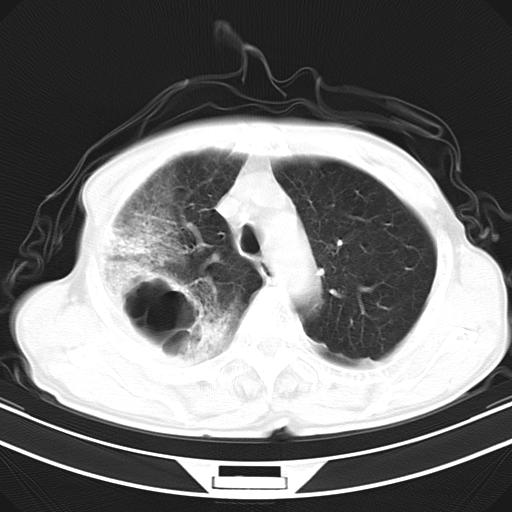

抗炎治疗10天后复查

影像所见:右上肺见一巨大厚壁空洞,内壁欠光整,右上肺广泛斑片状、大片状模糊阴影。

抗炎治疗10天后复查:右上肺模糊阴影明显减少。

诊断意见:考虑右上肺巨大含气囊肿并感染,建议继续治疗后复查。

影像所见:右上肺见一巨大厚壁空洞,并见分隔,内壁欠光整,右上肺广泛斑片状、大片状磨玻璃阴影。